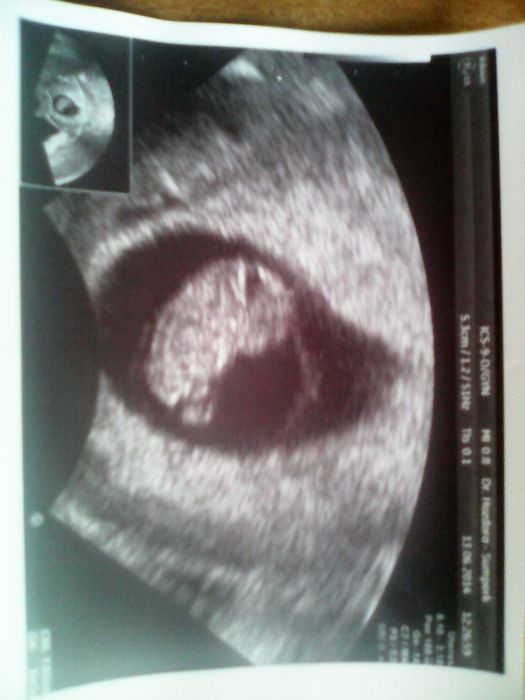

Holky. Tak je to za mnou,místo v 11.h.jsem se dostala na řadu po 12.h a ve 13.h.jsem byla konečně venku. Stálo to zato. MUDr.Marek nás vyfotil,v 7+6tt jsme velcí na 8+3tt,máme 1,92cm. Na další kontrolu jdu 14.7a hned další den na prvotrimestrální screening. Přikládáme foto

Jeee to je krasna fazolka :D